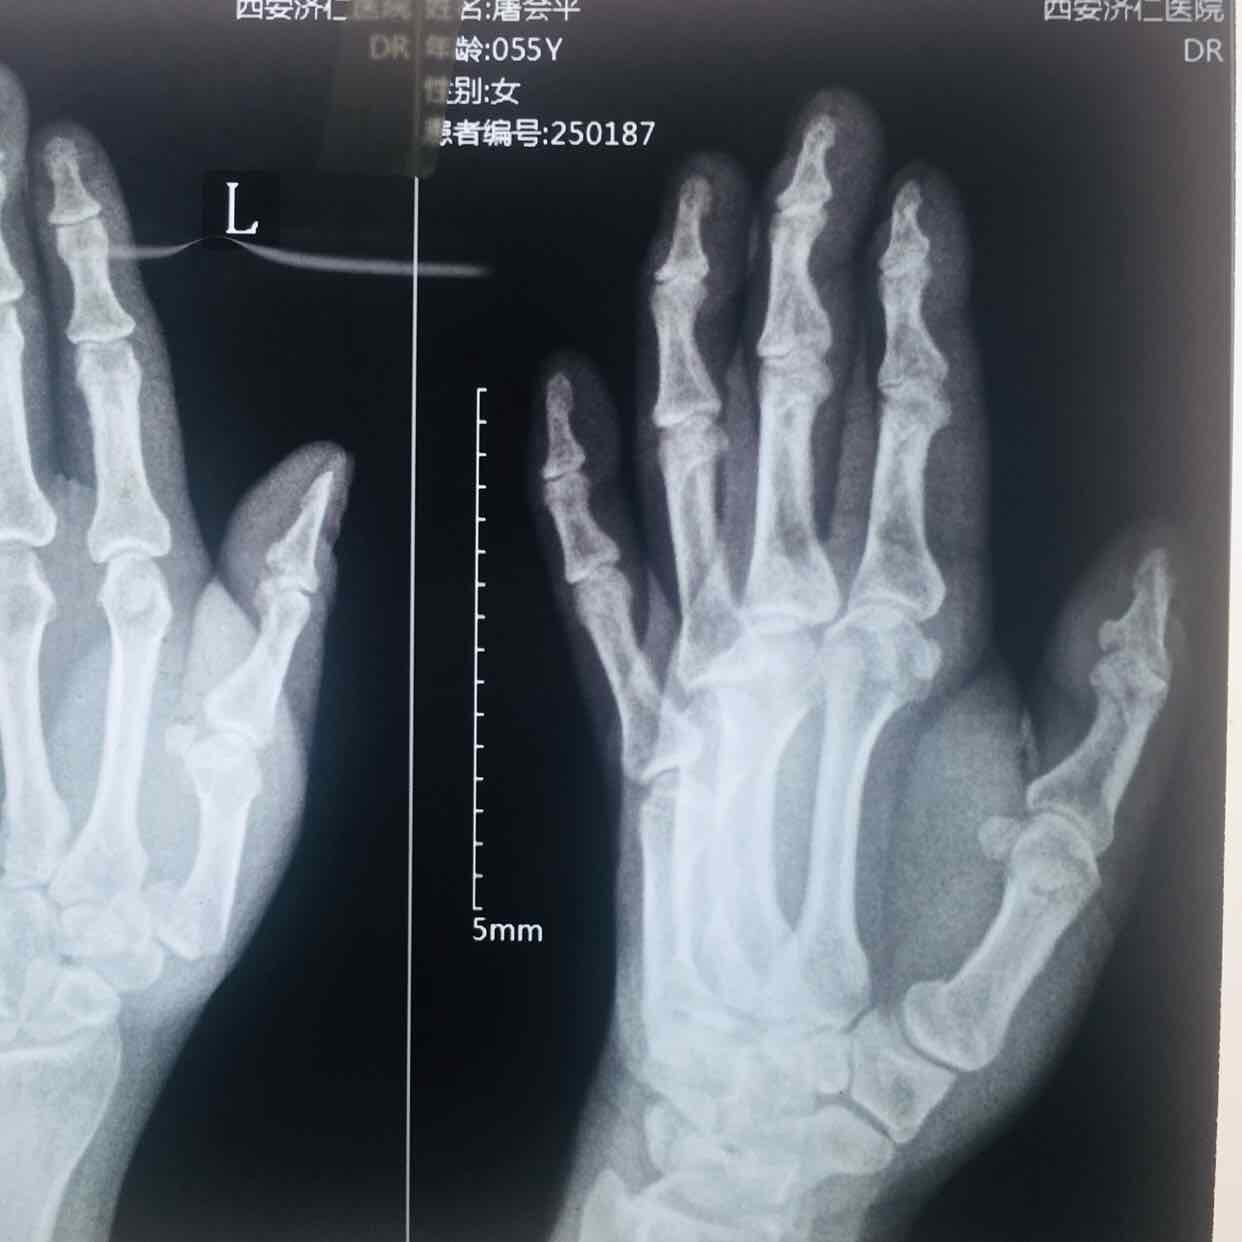

第一掌骨基底部骨折(微钢板固定)

摔伤后左手疼痛,活动受限1小时入院。既往身体健康,无特殊不良嗜好。

生命体征平稳,心肺复未见异常。左手部肿胀明显,局部皮色发红,皮温高,压痛及纵向叩击痛阳性,第一掌指关节活动受限,末梢血运感觉正常。

诊断左手第一掌骨基底部骨折在臂丛麻醉下行切复内固定术,术后抗炎消肿等处理,石膏托外固定。